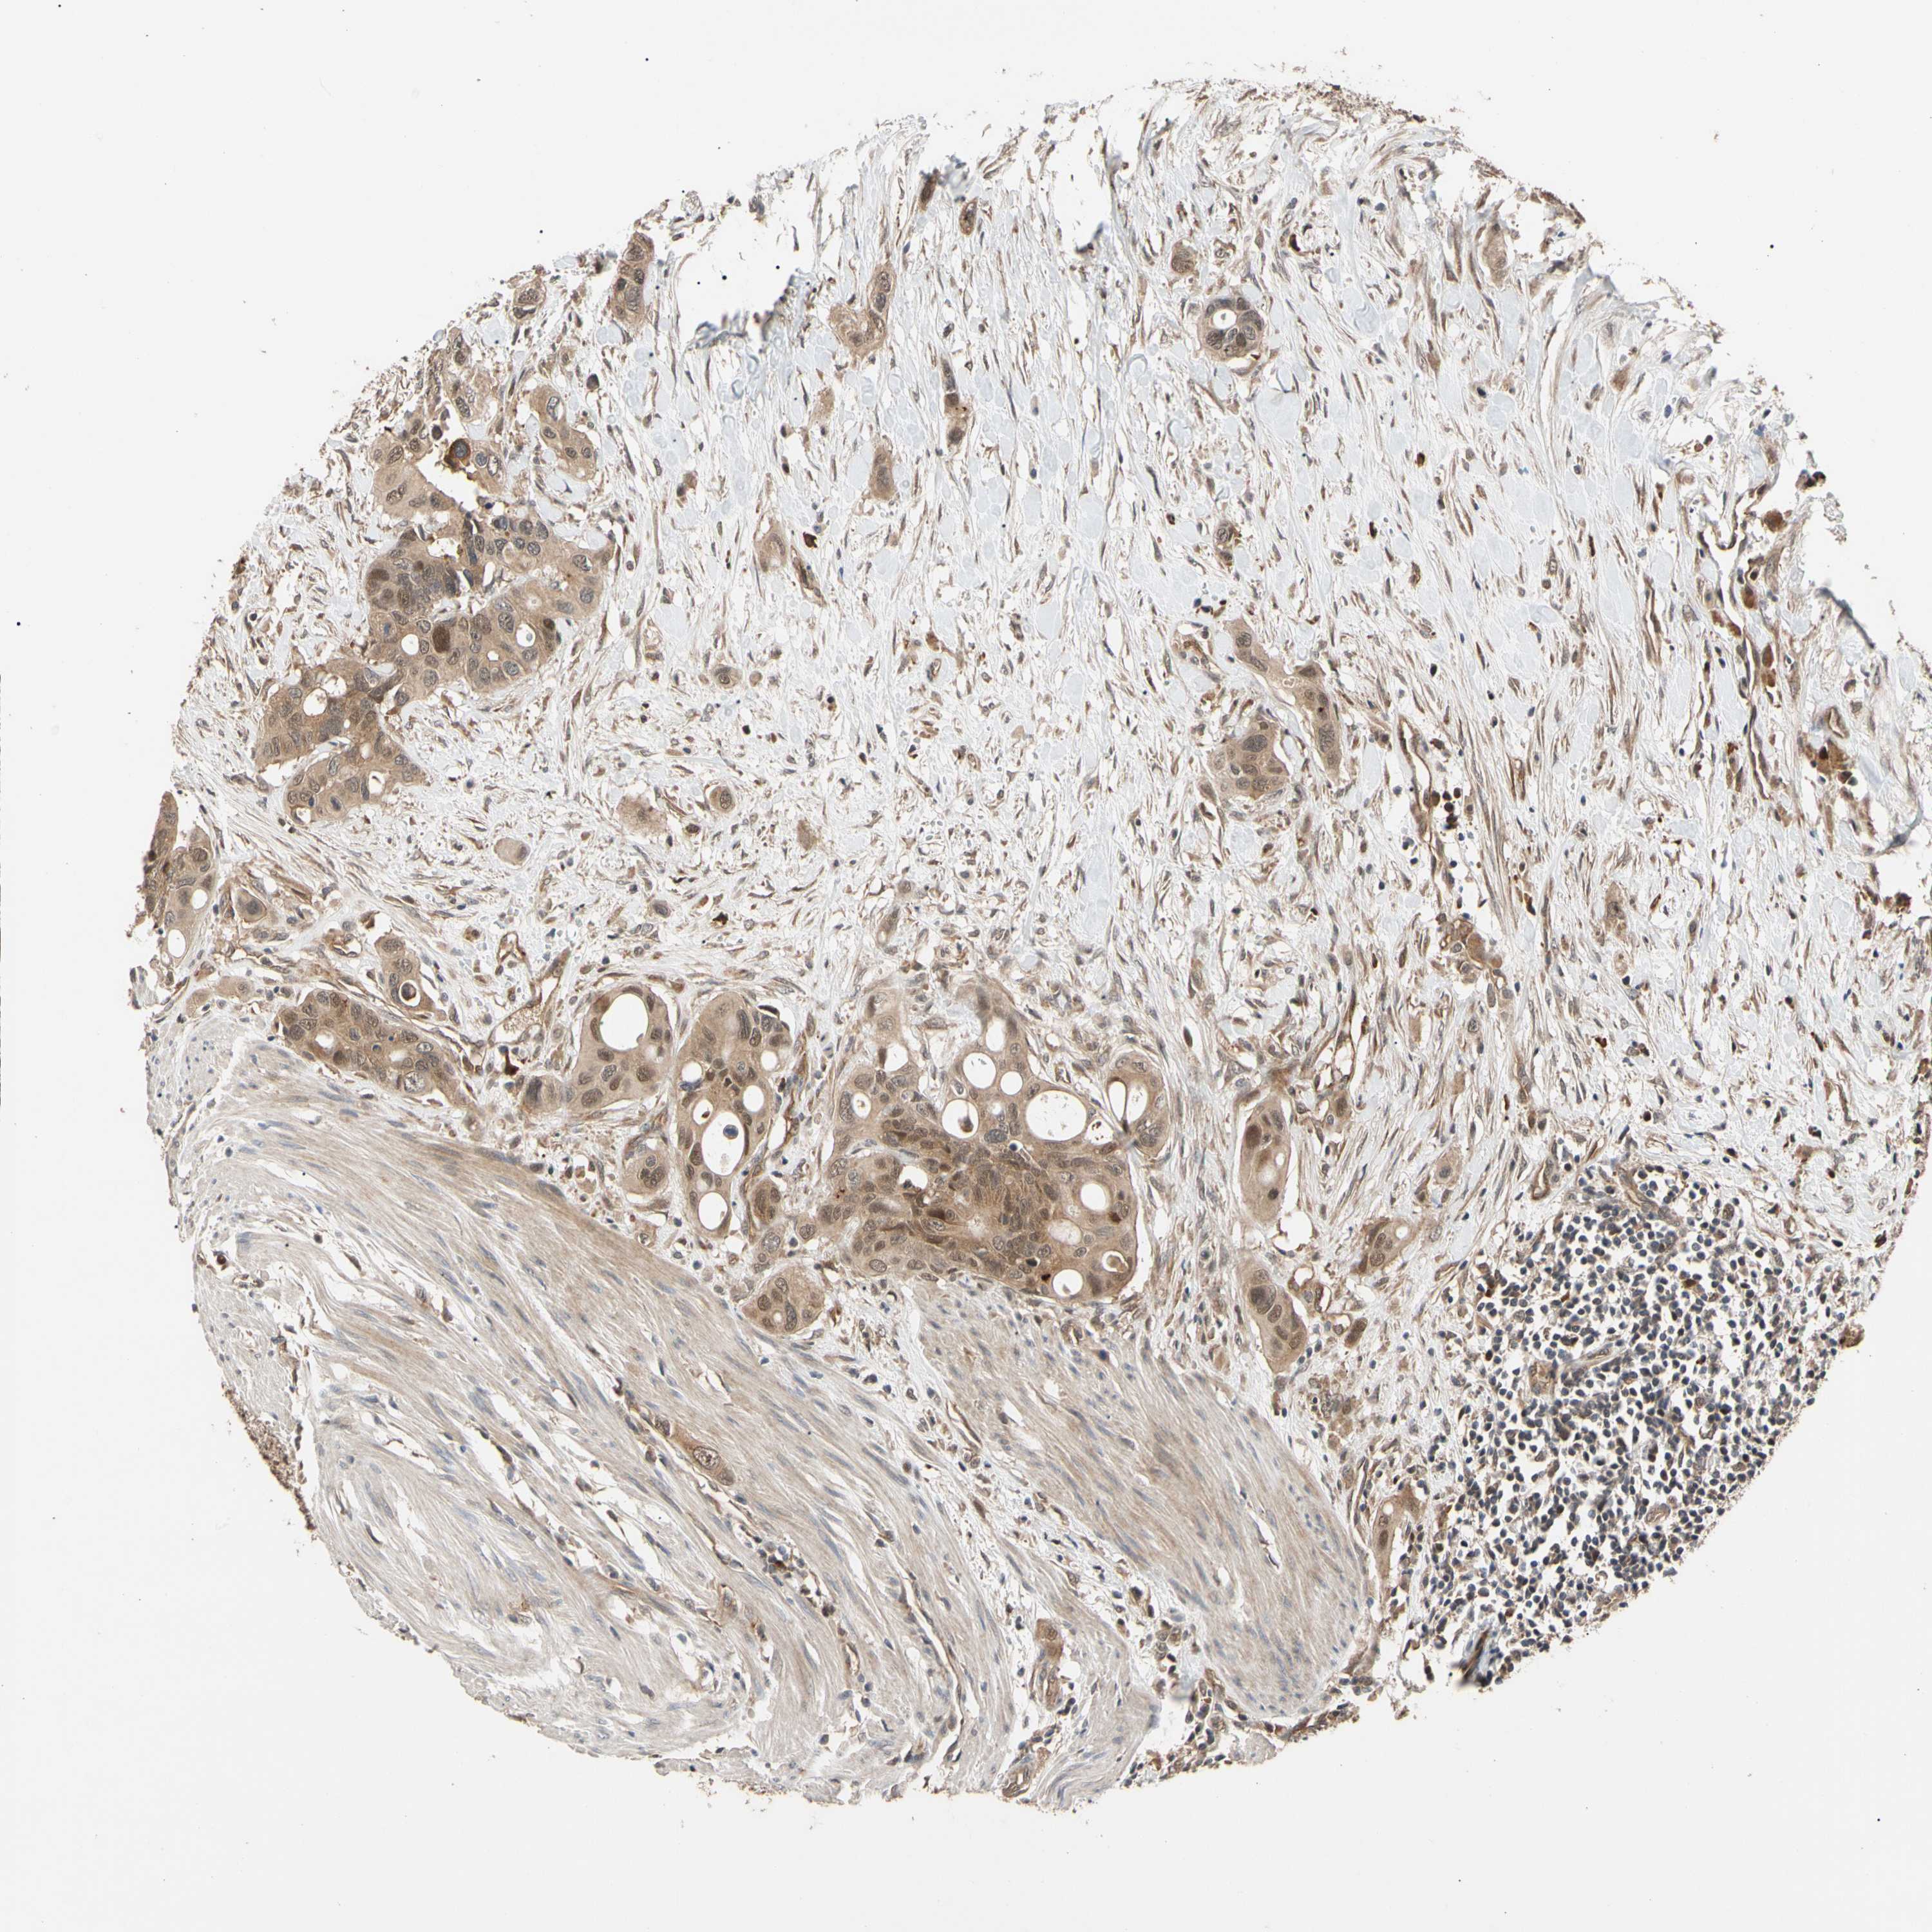

CANCER COLORECTAL CANCER Show tissue menu

Colorectal cancer

Human cancer

Colon adenocarcinoma